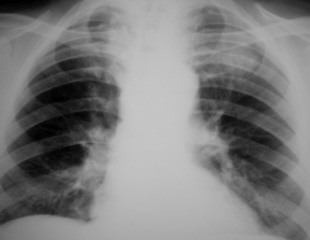

Исследование проведено на цифровом флюорографе «Ренекс-Флюоро». Иллюстрация 1 – прямая проекция. Иллюстрации 2, 3 – изучение изображения с увеличением.

Иллюстрация 1. Слева на уровне 1 межреберья определяется фокусная тень округлой формы средней интенсивности, с намечающейся «дорожкой» к корню левого лёгкого. В базальных отделах легочных полей, больше справа определяется усиление и обогащение легочного рисунка. Аорта несколько удлинена, незначительная гипертрофия левого желудочка.